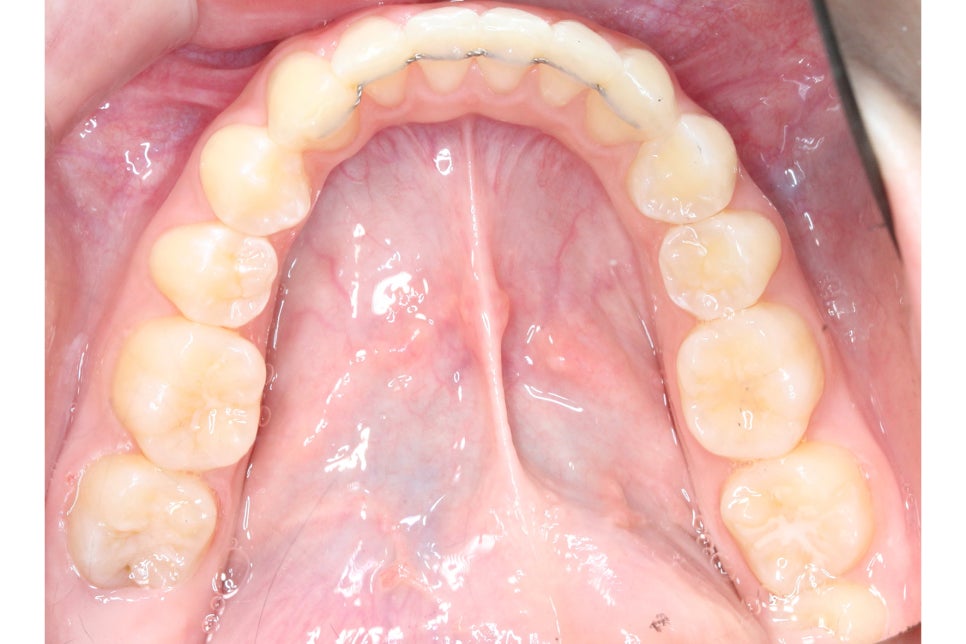

상악의 경우 교합면을 보면

교정 전 송곳니가 순측으로

뻐드러지듯 튀어나가 있던 모습에서

클리피씨교정 후 바른 위치로

바뀐 모습을 확인할 수 있는데요,

치아의 위치가 바르게 바뀌면서

전체적인 안모의 형태도

부드러운 u-라인을 형성한 모습입니다.

투디치과 환자분의 교정 후 아랫니의 모습을 보면

총생이 심했던 전치부 치열이 몰라볼 정도로

가지런해진 것을 확인할 수 있는데요,

삐뚤거리던 치아가 바르게 배열되면서

치석과 치태가 사라진 모습입니다.

전체적인 안모의 형태도 이상적인

곡선을 그리는 모습으로 비발치로 진행하였지만

비교적 단기간에 교정을 마무리할 수 있었는데요,